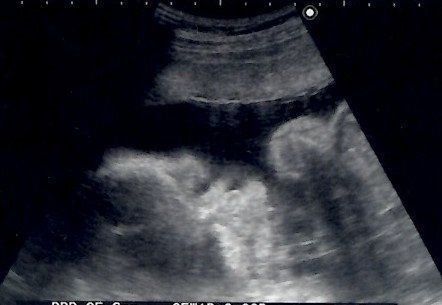

妊娠40週目のエコー写真 羊水の状態が悪くなり、計画出産が決定

出産の兆候がないまま予定日を過ぎ、赤ちゃんの体重はとうとう4000g越えに。病院での検査の結果、羊水の状態が良くないことがわかり、すぐに入院~出産することが決まりました。今思うと、当時は出産後の大変さを予想できないまま、楽観的な気持ちで病院に向かっていた自分が本当に情けないです。でも、もしその後の大変さを知っていたなら、おそらく出産に挑むことはできなかったかもしれないな、とも思います。